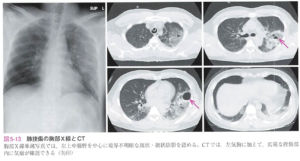

肺区域に従わない透過性低下、肺挫傷内部に気瘤を認める場合もある 受傷数時間後に異常陰影を認めることが多く、3〜4日後にはX線所見は消退することが多い |

肺挫傷 |

X線で診断できないOccult気胸が約20%存在する![]() |

気胸 |